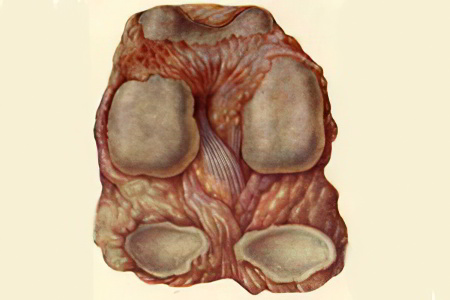

Инфекционное воспаление, или гнойный артрит

Одним из самых распространенных заболеваний тазобедренного сустава, с которым сталкиваются врачи, является…

Заболевание вызывается микобактериями туберкулёза. Оно бывает первичным, когда очаг туберкулёза формируется непосредственно в суставе, и вторичным, когда бактерии попадают в тазобедренный сустав через кровоток из лёгких или других поражённых органов. Чаще всего это заболевание встречается у ослабленных детей.

Симптомы

Туберкулёзный артрит развивается медленно и постепенно. На ранних стадиях ребёнок может испытывать быструю утомляемость и ограничивать физическую активность. Со временем наблюдается сглаживание ягодичной складки и атрофия мышц бедра. Подвижность в тазобедренном суставе ограничивается. Затем усиливаются болевые ощущения, и нога с поражённой стороны может казаться длиннее здоровой. В суставной полости накапливается воспалительная жидкость, которая может нагнаиваться. Гной, растворяя синовиальную оболочку тазобедренного сустава, выходит между мышцами, образуя холодный абсцесс.

Диагностика

Ребёнок проходит комплексное обследование для выявления возможных очагов туберкулёза в других органах. Для оценки степени повреждения головки бедренной кости применяется рентгенография.

Лечение

У детей рекомендуется консервативный подход к лечению. Он включает ограничение подвижности тазобедренного сустава с помощью высокой гипсовой повязки, охватывающей тело от груди до ступней. Также назначается курс противотуберкулёзных медикаментов.

Хирургическое вмешательство необходимо, если в мягких тканях образуется абсцесс. В этом случае его вскрывают и устанавливают дренаж для удаления гноя.